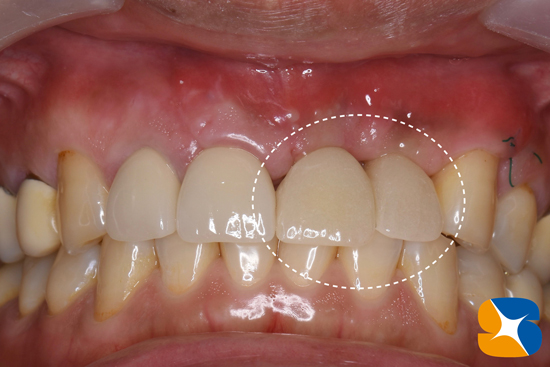

施術後、僅か2週間で仮のインプラントを装着しました。

噛み込みが強いため、仮歯の分厚さの調整は慎重に行っています。

かなり難度の高い施術でしたが、術後2ヶ月経った今も経過は良好です。

また、陥没していた歯茎も同時にボリュームアップしていますので最終結果が楽しみです。